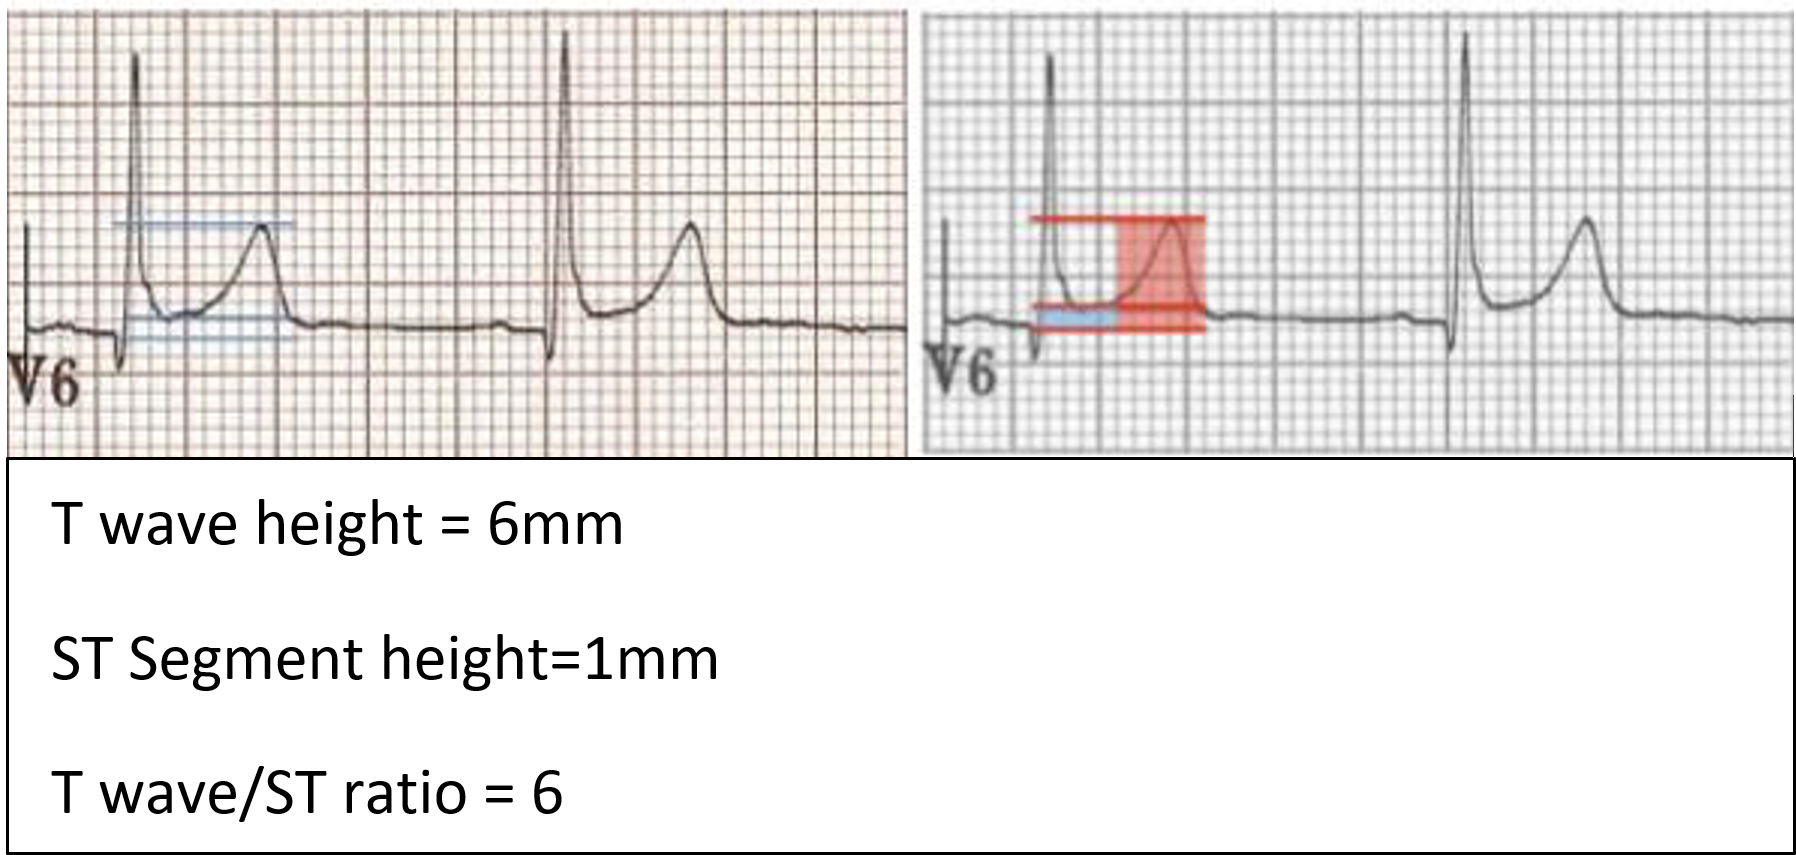

Differences between BER and ECG changes of pericarditis:

- ST elevation limited to precordial leads

- No PR depression

- Prominent T waves

- Ratio of T wave amplitude to ST elevation should be >4 if BER is present (the T wave in BER is normally 4 times the amplitude of the ST segment elevation, ie. ST segment elevation is less than 25% of the T wave amplitude in BER)

- ST segment elevation in BER resolved when the person exercise

- Notched J point elevation, AKA ‘fish hook’ pattern, best seen in lead V4